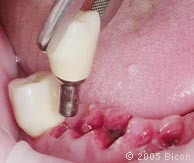

67. |

戴入一体化基台冠前的软组织袖口。 |

![]() |

68. |

口内粘接起来以前的一颗一体化基台冠和一个两单位悬臂基台冠。 |